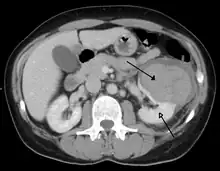

Abdominal trauma resulting in a right kidney contusion (open arrow) and blood surrounding the kidney (closed arrow) as seen on CT | |

Kidneys

The kidneys may also be injured; they are somewhat but not completely protected by the ribs.[6] Kidney lacerations and contusions may also occur.[13] Kidney injury, a common finding in children with blunt abdominal trauma, may be associated with bloody urine.[13] Kidney lacerations may be associated with urinoma or leakage of urine into the abdomen.[4] A shattered kidney is one with multiple lacerations and an associated fragmentation of the kidney tissue.[4]